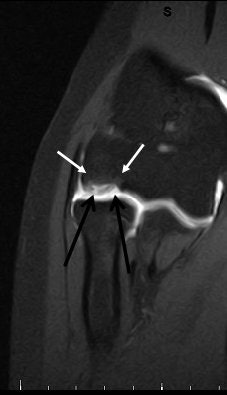

![]() |

| Above and below, OCD of the medial femoral condyle in a female child. Images courtesy of Dr. Douglas Beall. |